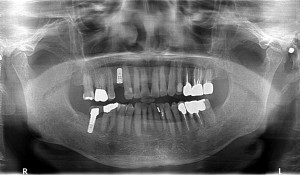

【50代 男性】

左下2番から右下7番まで欠損しておられ、

上顎は右上6番まで歯が確認出来る方でした。

CT画像を拝見すると十分に骨幅、骨の高さともに確認できましたので

インプラント埋入を4本で計画させていただき

スイス製ストローマンインプラントスタンダードプラスRNを

埋入させていただきました。

左下欠損部位は本日はご希望ではなかったので

右側臼歯部からインプラントを埋入させて頂きましたが

今後、左側も進めさせていただく予定をしております。

二ヵ月後にはアンカードブリッジを装着させて頂く予定で本日は終了致しました。